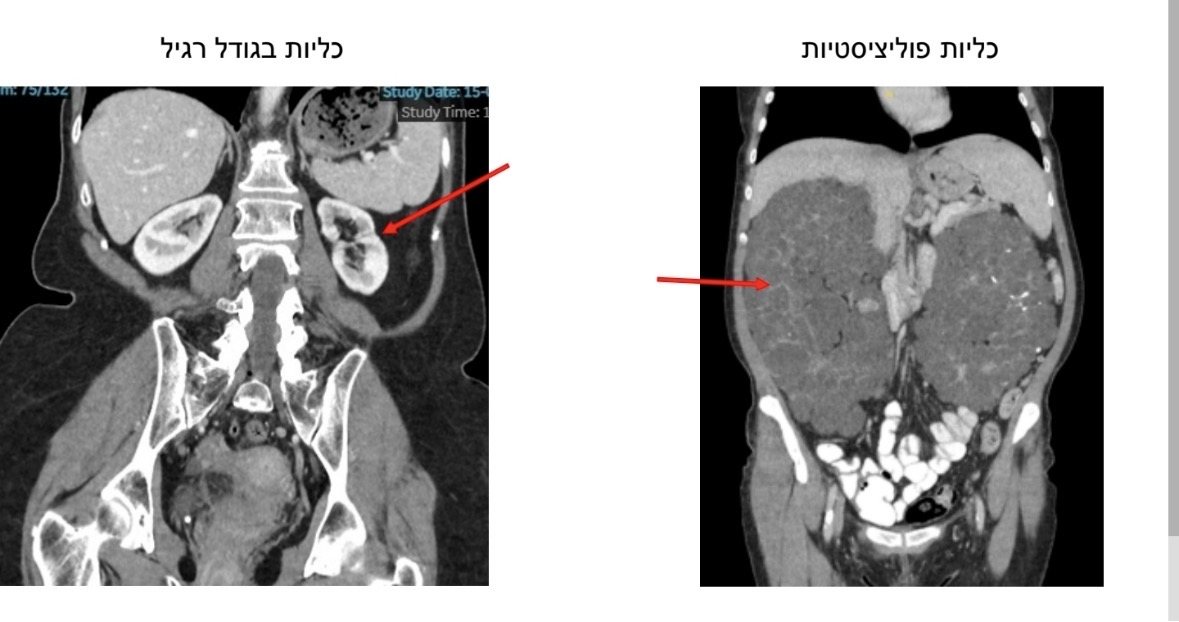

תושבת אשדוד בת 51 עברה ניתוח נדיר ומורכב במיוחד לכריתת שתי כליות פוליציסטיות עצומות. רגע לפני החג, מבחינתה זו ממש יציאה מעבדות לחירות. אחרי שנים של סבל מכאבים, לחץ פנימי וקושי לאכול, רק מספר ימים לאחר הניתוח והיא כבר מדווחת על שיפור משמעותי ולראשונה מזה שנים ללא כאבים.

אוליאנה שבלה (51, סבתא ל-2 נכדים), נולדה עם מחלה גנטית בה רקמת הכליות הופכת לציסטות מרובות ובהדרגה מאבדות את תפקודן, עד מצב סופי ובלתי הפיך של כליות פוליציסטיות אשר אינן מסוגלות לבצע סינון תקין של הדם מרעלים. לאור זאת מזה כ-15 שנים, שבלה עוברת דיאליזה, 3 פעמים בשבוע, בבי״ח אסותא אשדוד. במקביל, בשנים האחרונות, הכליות שלה (לא תפקודיות) המשיכו לגדול והגיעו לממדים קיצוניים עד למילוי מרבית חלל הבטן. היא סבלה מכאבים קשים, זיהומים, בצקות וקושי במאמץ ודיווחה על פגיעה משמעותית באיכות החיים.

שתי הכליות יחד שקלו יותר מ-5 ק"ג. כאשר משקל כליה בריאה נע בין 120 ל־170 גרם בלבד.

אורכן של הכליות הגיע ל- 35 ס״מ לעומת כ 10 ס״מ בכליות בריאות.

טווח המשקל המקובל של כליות פוליציסטיות נע בין כ־1.6 ל־2.4 ק"ג – מה שהופך את המקרה הנוכחי לנדיר במיוחד.

מדובר במקרה נדיר ביותר, כאשר אחת הכליות הפוליציסטיות שהוסרו נמנית עם הגדולות שתועדו בספרות המקצועית בשנים האחרונות.